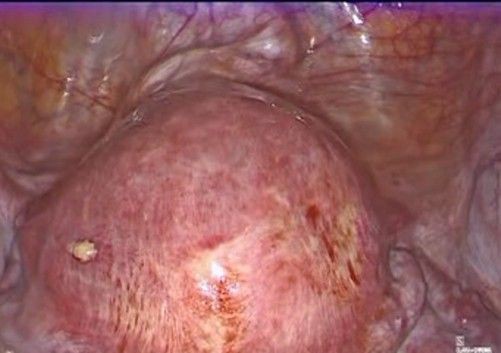

- Preparation and access (Figure 2): The patient is placed in a modified dorsal lithotomy position, with a slight Trendelenburg position to facilitate pelvic exposure. Pneumoperitoneum is installed through the Palmer point access, and trocars are placed. The abdominal and pelvic cavities are assessed, identifying the uterus, adnexa, bladder, and rectum.

Figure 3: exposure of the lower uterine segment